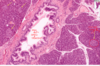

This one’s a little confusing – this is your pyloric stomach. Here’s your muscularis mucosa [line] which comes across and gets interrupted. Down here (A) we have glands below the muscularis mucosa, and I already told you there are only two places in the GI tract where you have submucosal glands: the esophagus and the duodenum.

This is the gastroduodenal junction: you have surface mucus cells (C) but over here you’re going to have a simple columnar epith with goblet cells here (B). [Note, I think he pointed to the wrong ones because later in the lecture he says that the intestine has the goblet cells, so the correction has been applied here].

The submucosal glands in the duodenum are the glands of Brunner.